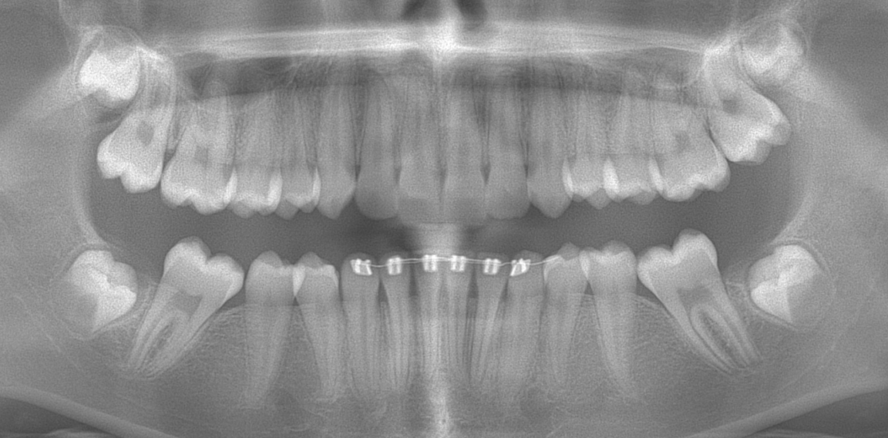

Molaren-Inzisiven-Hypomineralisation (MIH) ist neben Karies eine häufige Erkrankung der Zähne von Kindern und Jugendlichen. Sollten alle konservierenden Behandlungsmöglichkeiten ausgeschöpft sein und die Indikation zur Extraktion gestellt werden, kann eine zweistufige Extraktion mit Hemisektion und folgendem kieferorthopädischen Lückenschluss in Betracht gezogen werden.